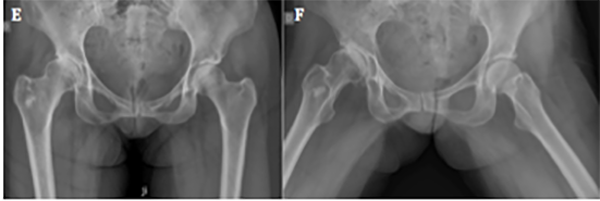

Se detectaron seis fallas (14.6%): dos casos progresaron a reemplazo total de cadera a los nueve y catorce meses postoperatorios (fig. 4), y cuatro presentaban síntomas persistentes luego de los nueve meses de la cirugía, los cuales, a la fecha, no requirieron de un procedimiento adicional.

Figura 4: Paciente femenina, cincuenta y siete años. A) Rx frente de ambas caderas, se observa esclerosis subcondral acentuada y signo de cross-over. B) Rx perfil de ambas caderas. Se visualiza el aplanamiento de la transición cabeza-cuello en ambos fémures. C) Rx ambas caderas, frente. Evolución a los tres meses postoperatorios. Se observa pinzamiento de la luz articular de cadera derecha. D) En la radiografía de perfil se constata una buena resección del CAM y del quiste de impacto en cabeza femoral, con progresión de la artrosis. E) Rx de ambas caderas, frente. A los seis meses de la cirugía se presenta a la consulta con coxartrosis polar superior. F) En el perfil se puede observar luz articular colapsada en el borde superoexterno de cadera derecha. G) Rx frente de ambas caderas. A los nueve meses de evolución se realizó la artroplastia total de cadera derecha.